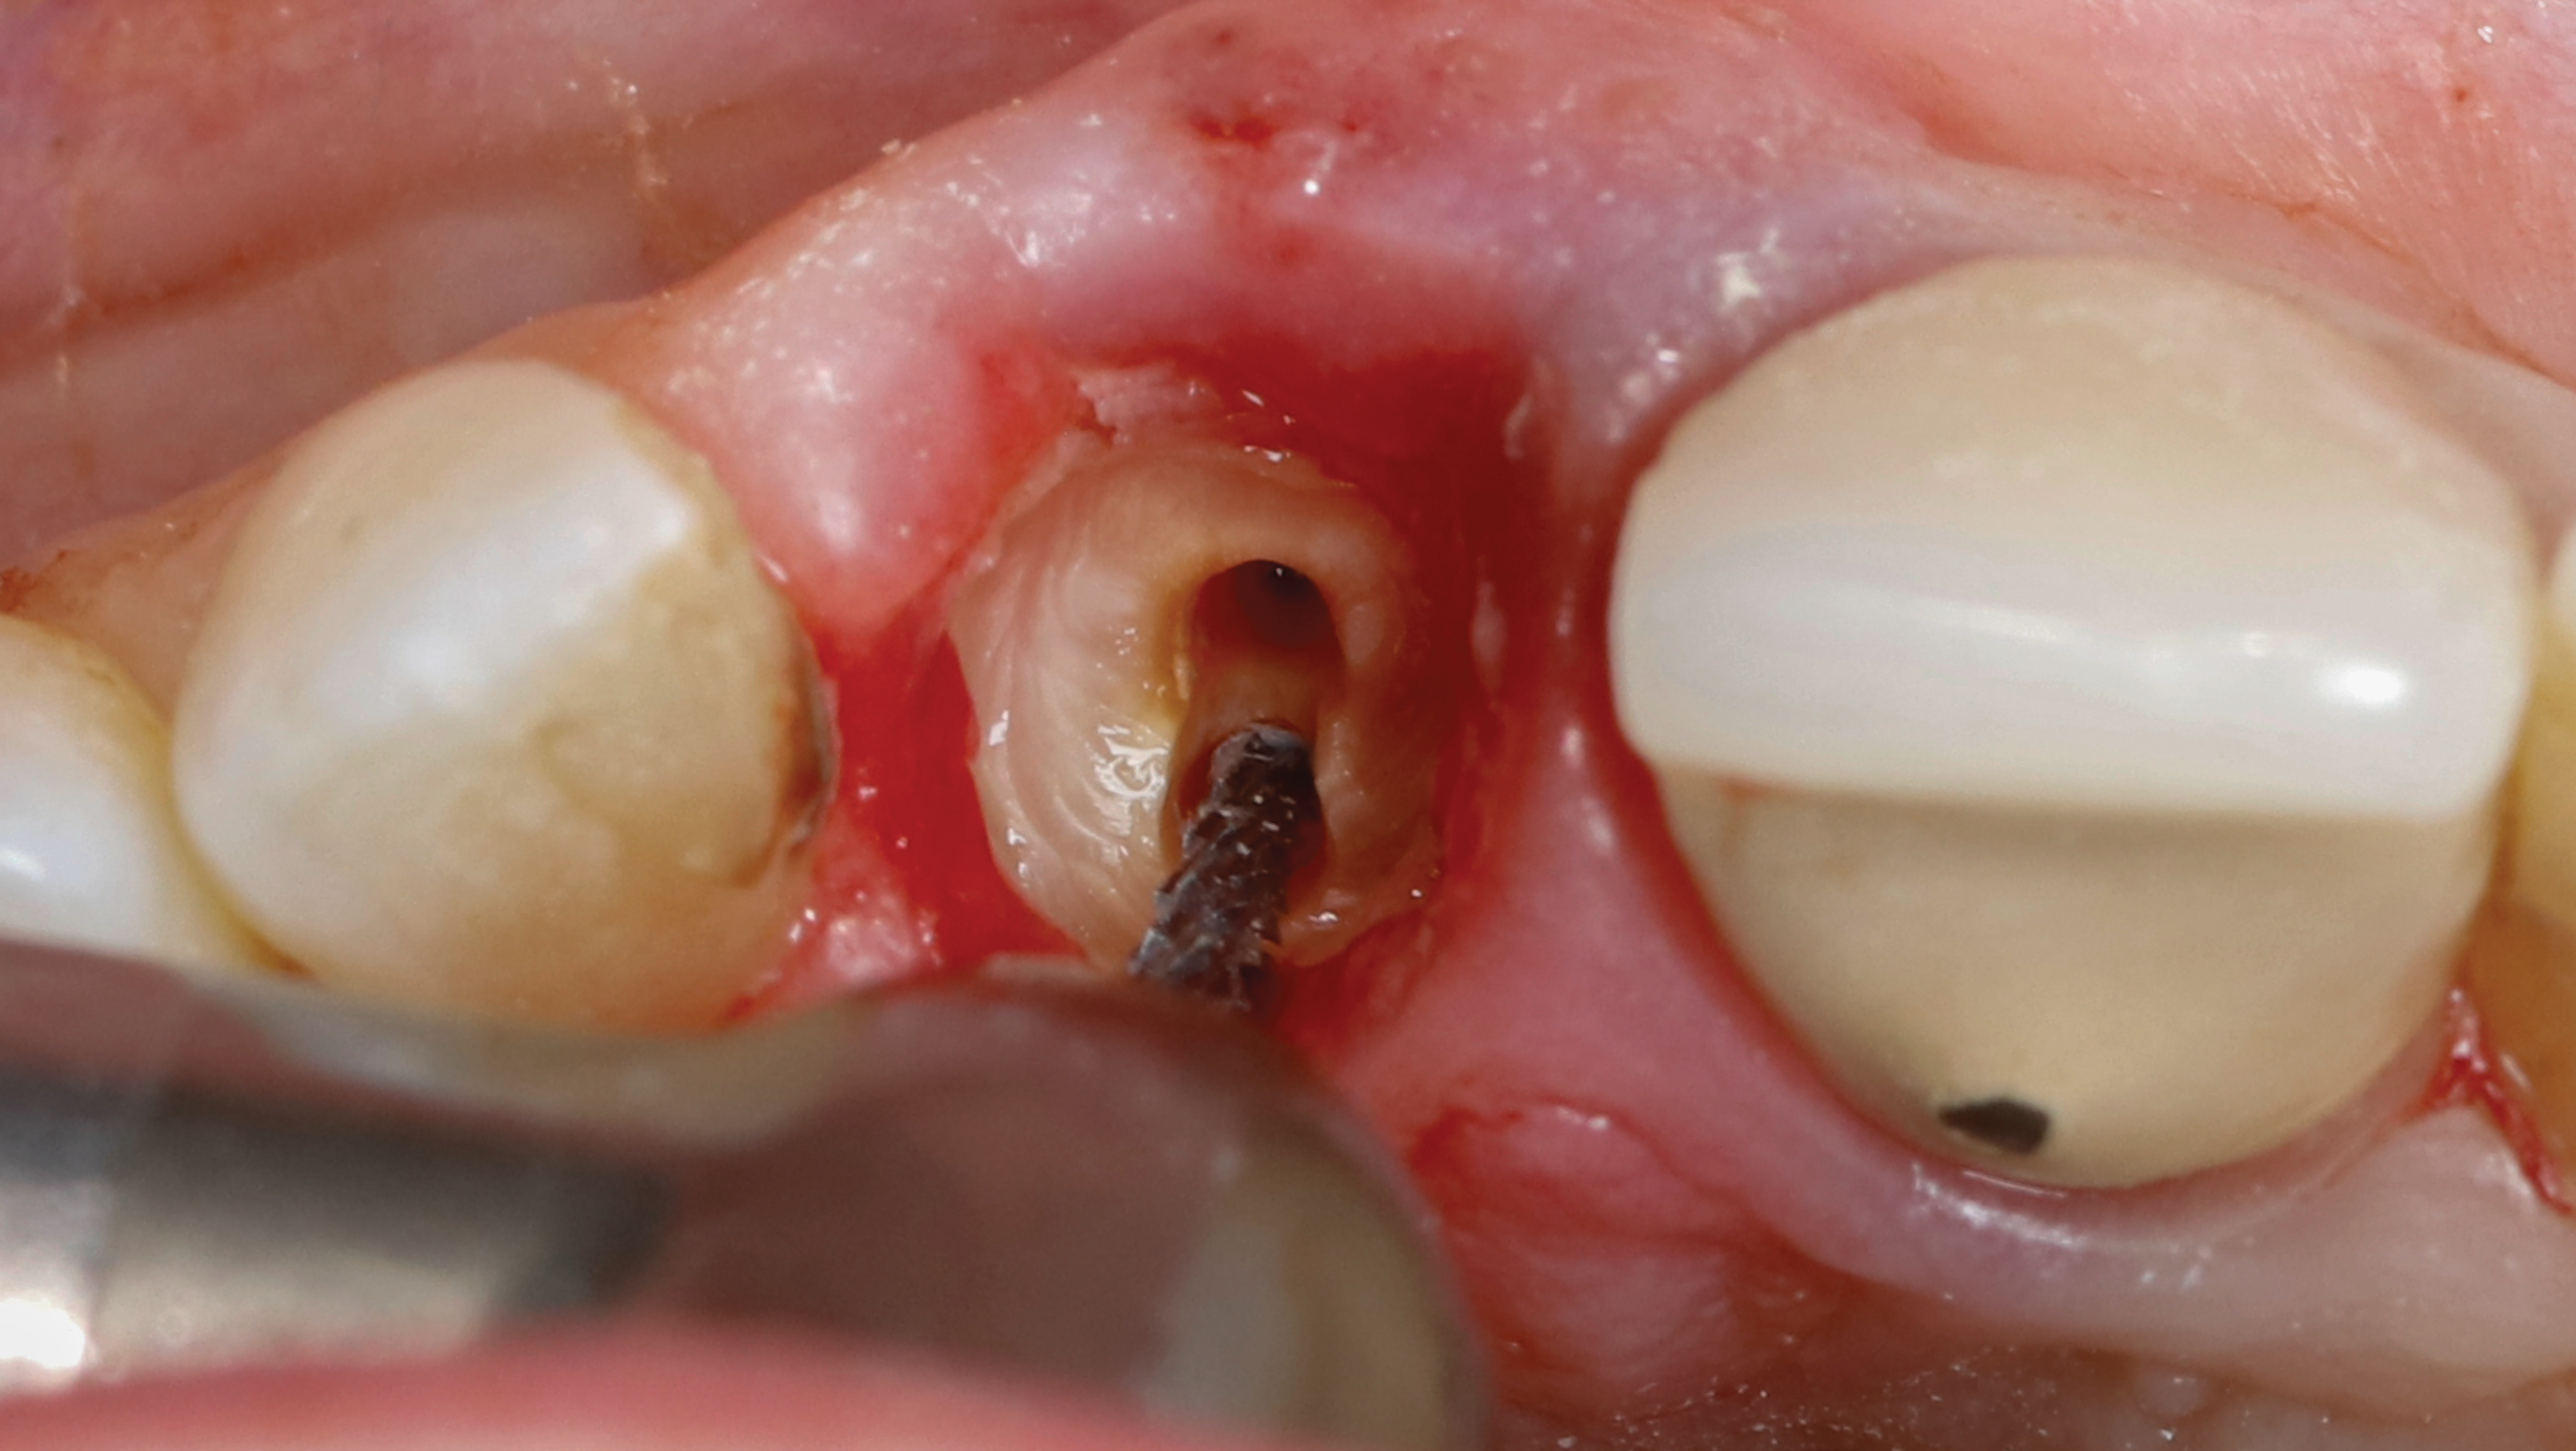

Fig 6. SPOT Step 2: The restorative zone is established using a diamond wheel bur (Meisinger 909G-031) to flatten the root to bone level, working from inside to outside.

Figure 6

Fig 13. SPOT Step 5: The mesial-distal root split is prepared with a long shanked carbide bur (Meisinger HM34IL-012) without violating the implant osteotomy.

Figure 13

Fig 14. SPOT Step 5, cont’d: The palatal root section is gently removed, and the shield height is reduced to bone level approximately 2 mm to 3 mm subgingivally using a shaping bur (Megagen 3DD50). The shield thickness is reduced to 1.5 mm to 2 mm using a round diamond bur (Megagen 2DD3034, as shown); further shield thickness reduction could be finalized using a diamond shaping bur (Megagen 1DD1911). The coronal shield chamfer is created to allow for an “S”-shaped restorative space using a diamond chamfer shaping bur (Megagen GD40G).

Figure 14